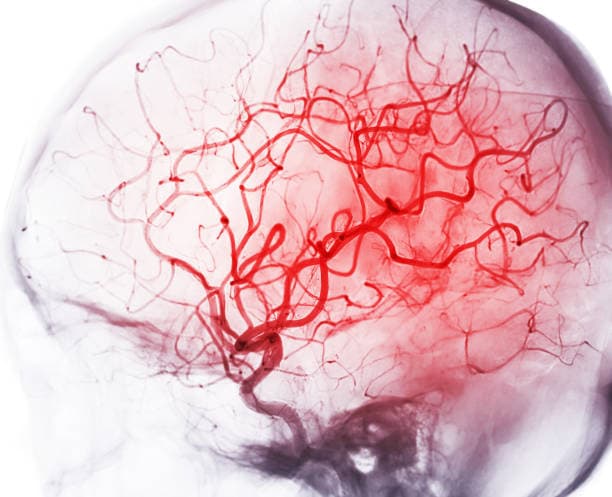

Angiography is a diagnostic imaging technique that visualizes the interior of blood vessels and organs, particularly the arteries and veins, by utilizing contrast dye and advanced imaging methods. During an angiography procedure, a contrast agent—usually iodine-based—is injected into the bloodstream through a catheter inserted into a major blood vessel. As the dye travels through the circulatory system, specialized imaging equipment, such as X-ray fluoroscopy or computed tomography, captures detailed pictures of blood flow in real time. The resulting images enable physicians to detect abnormalities such as blockages, narrowing (stenosis), aneurysms, or other vascular anomalies that may contribute to serious cardiovascular conditions. By producing high-resolution images of the vascular network, angiography facilitates early diagnosis and treatment planning for conditions like coronary artery disease, stroke, and peripheral artery disease. In addition to its diagnostic value, the technique also provides guidance during interventional procedures such as angioplasty or stent placement. Overall, angiography is a critical tool in modern cardiovascular medicine, offering precise visualization that improves diagnostic accuracy, guides therapeutic decisions, and ultimately contributes to better patient outcomes by enabling timely, targeted treatments.

Angiography is required as a critical diagnostic tool for evaluating the vascular system and accurately identifying irregularities that could compromise health. This imaging technique is used to locate obstructions, narrowings, or abnormalities in blood vessels that may lead to serious conditions such as coronary artery disease, strokes, and peripheral artery disease. Through the injection of a contrast dye and the use of advanced imaging equipment, angiography provides high-resolution, real-time images that allow physicians to thoroughly assess blood flow and vessel integrity. The detailed visualization obtained through angiography is essential for making informed decisions regarding further therapeutic interventions, such as angioplasty or stent placement. In addition, angiography aids in the planning of surgical procedures by mapping the exact location and severity of vascular lesions, ensuring that treatments are both precise and minimally invasive. By enabling early detection of vascular problems, angiography plays a vital role in preventing the progression of potentially life-threatening conditions. Angiography risks & benefits

Angiography is a pivotal diagnostic procedure that provides detailed images of the vascular system and plays a critical role in identifying blockages, narrowing, or other abnormalities in the blood vessels. Through the injection of contrast dye and the application of advanced imaging techniques, such as X-ray fluoroscopy or CT scanning, it offers precise visualization invaluable for diagnosing conditions like coronary artery disease, peripheral arterial disease, aneurysms, and strokes. This detailed imaging aids healthcare professionals in planning subsequent interventions, including minimally invasive treatments like angioplasty or stent placement, thereby improving patient outcomes and potentially saving lives. The benefits of angiography lie in its ability to detect vascular issues early, enabling proactive management of serious cardiovascular conditions. However, as with any invasive procedure, certain risks must be considered. These risks include allergic reactions to the contrast dye, bleeding, infection, or vessel damage at the catheter insertion site. Additionally, patients are exposed to a modest amount of ionizing radiation during the procedure.

Angiography is a diagnostic imaging technique that involves injecting a contrast dye into the bloodstream and using X-ray or CT imaging to capture detailed visuals of blood vessels. This minimally invasive procedure provides high-resolution images that allow physicians to detect obstructions, narrowings, aneurysms, and other vascular anomalies. Angiography serves as a vital roadmap, enabling clinicians to precisely identify problem areas within the circulatory system and plan subsequent interventions.